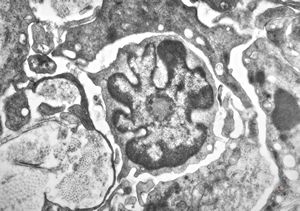

M, 70y. | mycosis fungoides - Sézary cell